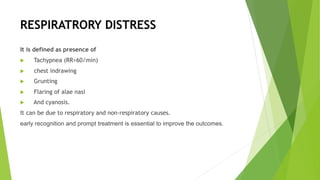

This document discusses respiratory distress and respiratory distress syndrome in neonates. It defines respiratory distress and describes the clinical signs. Various pulmonary and non-pulmonary causes are outlined. Respiratory distress syndrome, also known as hyaline membrane disease, is described in detail, including risk factors, pathophysiology, clinical presentation, investigations, complications, prevention, and treatment approaches like surfactant administration and nasal continuous positive airway pressure. The prognosis depends on gestational age and quality of care provided.